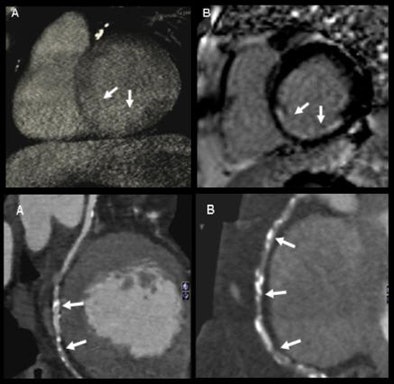

| Qualitative analysis: CT perfusion correctly classified 54 perfusion defects. Values for detecting myocardial perfusion defects at CT (versus SPECT) compared to MRI were as follows: 86% (84%) sensitivity, 98% (92%) specificity, 93% (88%) positive predictive value, and 94% (92%) negative predictive value. |

| Semiquantitative analysis: There were significant differences in upslope of signal intensity over time curve between normal and ischemic myocardium both with CT (above) and MRI (below). |

| Absolute quantification: Quantitative analysis showed significant differences in myocardial blood flow between normal and hypoperfused myocardium (p < 0.001); moderate correlation between absolute myocardial blood-flow quantification and upslope of signal intensity over time curves (r = 0.47, p < 0.01); and moderate correlation between myocardial blood flow and semiquantitative upslope for hypoperfused and normal myocardium (r = 0.41, p < 0.01 versus r = 0.43, p < 0.01). |